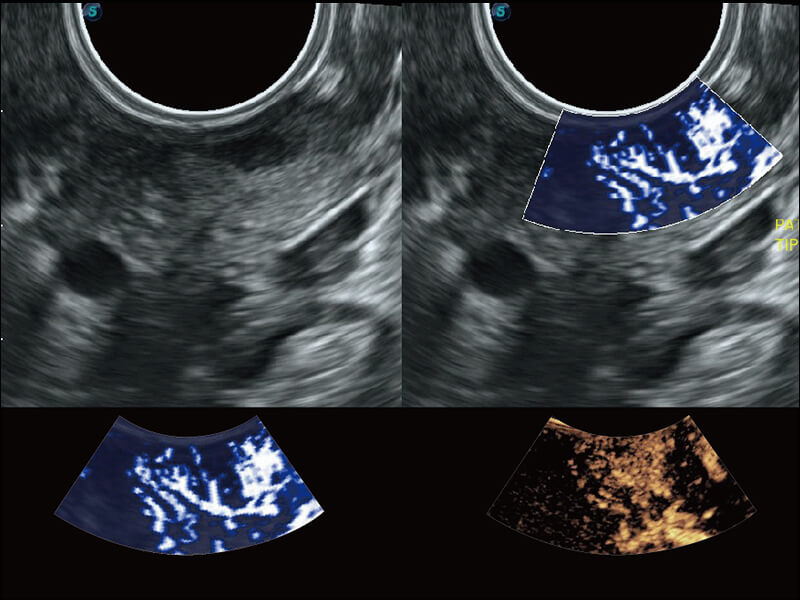

彩色多普勒超声诊断系统

S60探头工艺,从前端信号处理每一个环节采集无损声学数据,真实还原组织原貌,再现解剖细节。

超宽频带技术,为容积成像带来优质的二维图像基础,为您呈现丰富的结构细节,栩栩如生地展示宝宝的宫内形态以及各种组织的立体结构。